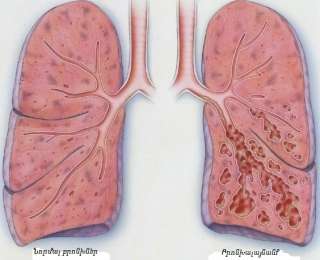

Երևի դժվար թե հանդիպի այնպիսի մարդ, ով իր կյանքի ընթացքում բախված չլինի կրծքային թաց հազի խնդրի։

Երևի դժվար թե հանդիպի այնպիսի մարդ, ով իր կյանքի ընթացքում բախված չլինի կրծքային թաց հազի խնդրի։

Դրա առաջացման պատճառները տարբեր կարող են լինել՝ ծխելուց մինչև բրոնխիտ և թոքաբորբ։